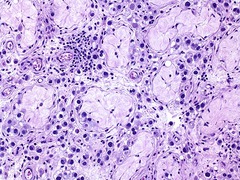

fat necrosis lost nuclei, vague cellular outlines, pale cytoplasm on H&E stain

Front

type of necrosis? morphologic features

Back